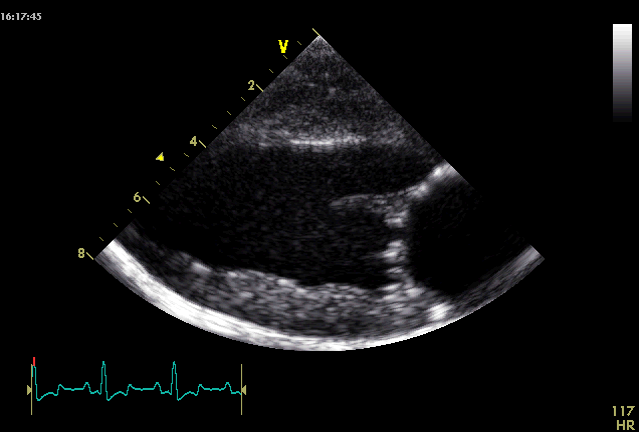

What view is this?

Right parasternal long axis 4 chamber